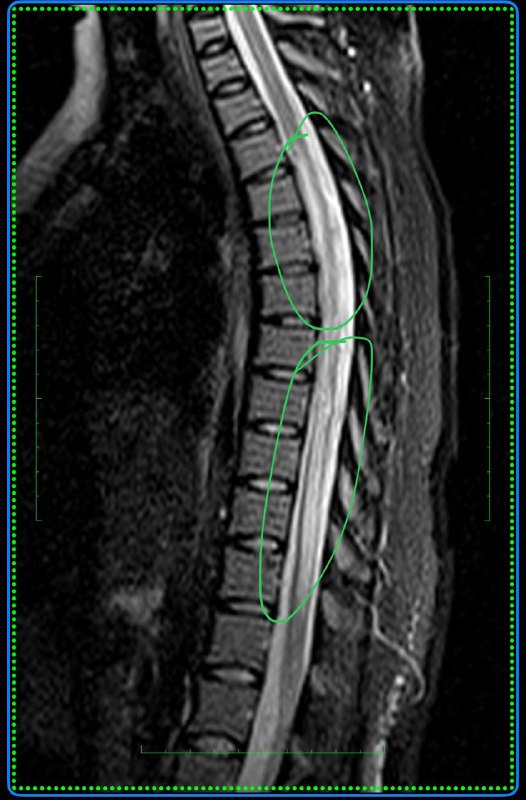

Анапластическая менингиома намета мозжечка справа с оболочечной спинальной диссеминацией у пациента 36 лет.